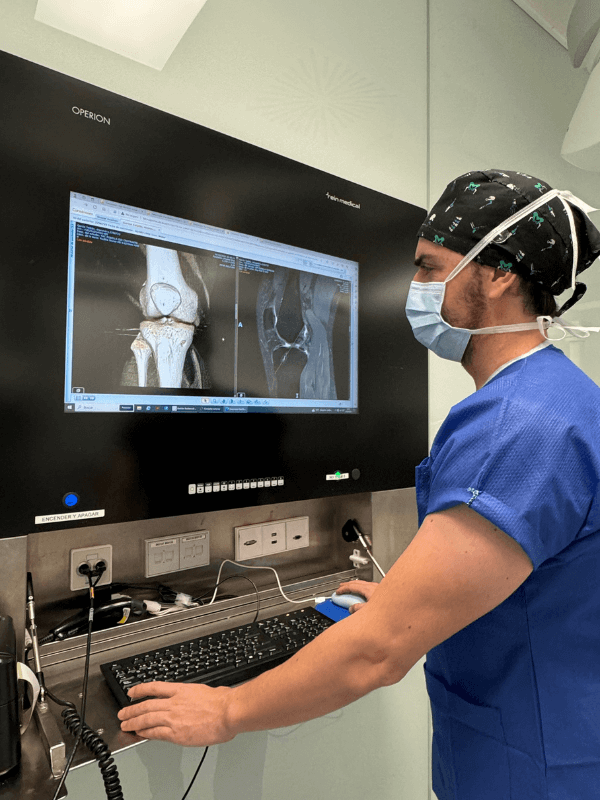

Artroscopia de rodilla

Procedimiento mínimamente invasivo que permite visualizar y tratar problemas dentro de la articulación de la rodilla. Con esta técnica, diagnosticamos y tratamos lesiones de tejidos blandos, cartílago y ligamentos con precisión, resultando en una recuperación más rápida y menos dolor para el paciente.

El Dr. Manuel Aliaga Guerrero es un reputado traumatólogo y cirujano ortopédico en Madrid. Actualmente, forma parte del cuadro médico de la Unidad de Traumatología del Hospital Universitario Fundación Jiménez Díaz, donde es experto en patología de rodilla, incluyendo la cirugía de rodilla, la artroscopia de rodilla, la artroplastia, lesiones deportivas de rodilla o en la reparación y/o preservación del cartílago.